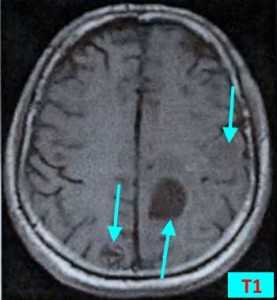

Т1 ВИ (без контрастного усиления)

- Изоинтенсивный либо умеренно гипоинтенсивный сигнал по отношению к белому веществу мозга от активной части опухоли

- Гипоинтенсивный сигнал от центральной зоны (некроза и распада)

Т2 ВИ

- Гиперинтенсивный сигнал от центрального участка метастаза

- Повышение интенсивности сигнала от отечных тканей мозга, окружающих вторичную опухоль, вследствие чего метастазы становятся более четкими на изображениях

Метастазы головного мозга на МРТ. Фото. Определяются множественные метастазы в мозг при раке легкого: слева в режиме Т1-ВИ в виде гипоинтенсивных образований, справа — в режиме Т2-ВИ виде множественных участков повышенного сигнала, окруженных зоной перифокального отека. У пациента подтверждена первичная опухоль легкого.